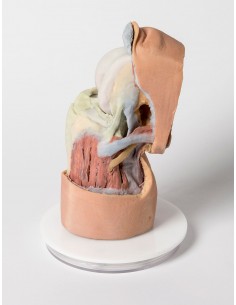

3D Anatomy 1.0 - Extremidades inferiores

Disección profunda del miembro inferior Erler Zimmer 3D anatomy Series MP1809